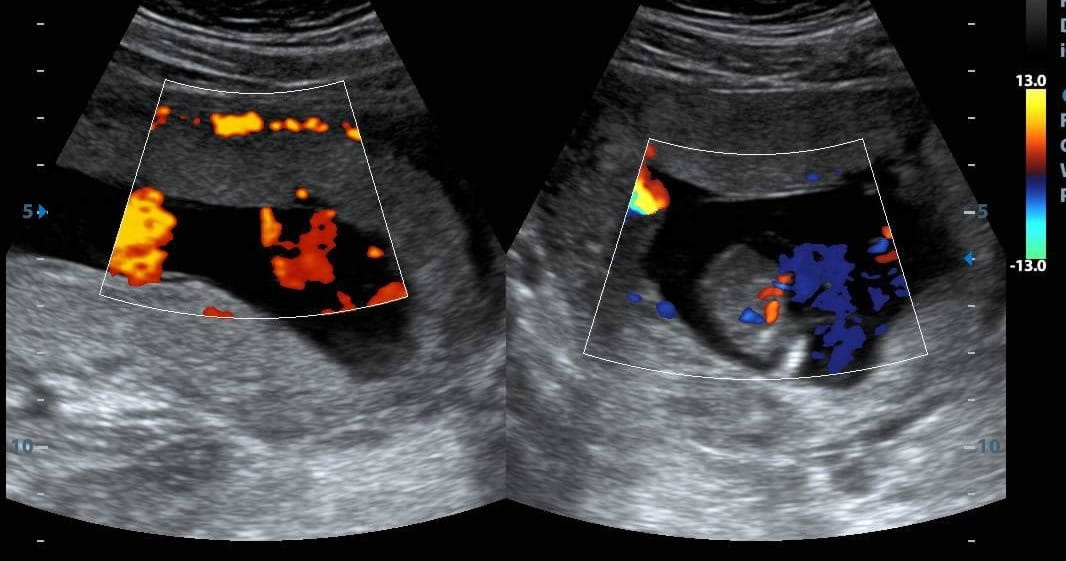

Ecografías del embarazo

Precisión médica y tecnología de avanzada para acompañar cada etapa del embarazo y cuidar lo más importante: tu bebé.